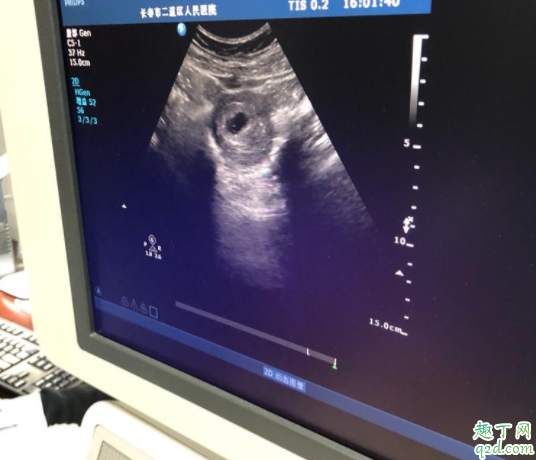

媽媽們早孕期間在去做b超檢查時,除了要關(guān)心胎心、胎芽,還是注意的就是卵黃囊了,它對于胎芽的發(fā)育是非常有必要的。那么胎芽和卵黃囊之間的關(guān)系是什么樣的呢?

卵黃囊是在懷孕期間妊娠囊中最早出現(xiàn)的結(jié)構(gòu),大概在懷孕5周時候出現(xiàn)并逐漸增大,給胎芽提供營養(yǎng),在12周后逐漸自行消失。

早孕檢查可以做經(jīng)腹部婦科彩超和經(jīng)陰道婦科彩超。兩個檢查都是同樣的檢查原理,都是利于超聲技術(shù)。只是兩個檢查的檢查途徑不一樣。經(jīng)腹部婦科超聲需要憋尿,經(jīng)陰道婦科彩超需要排空膀胱。但是經(jīng)陰道婦科彩超干擾更小,能夠早一周看見卵黃囊、胚芽和胎心。